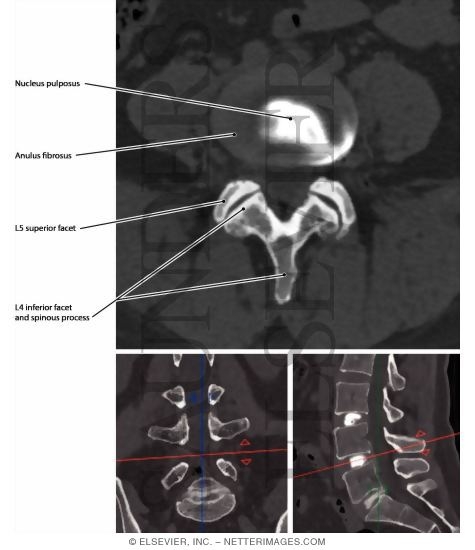

Radiologic Anatomy - Weber 1E

Please Note: While the images shown will be very similar to the images published in Radiologic Anatomy - Weber 1E, please realize that the text of the labels may differ.